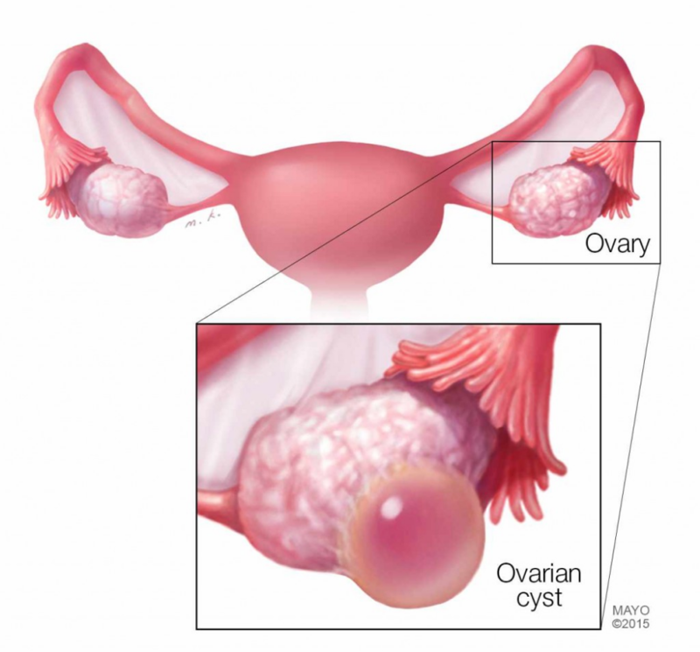

قبل از توضیح در مورد کیست هموراژیک تخمدان؟ لازم است بدانید که کیست تخمدان بیماری زنانهای است که از تشکیل یک یا چندین کیست غیرطبیعی در تخمدان سرچشمه میگیرد. کیستهای تخمدان ساکهایی حاوی مایع هستند که درون تخمدان یا روی آن رشد می کنند.

دو تخمدان شما در دو طرف رحم شما قرار دارند. هر کدام به اندازه و شکل یک بادام هستند. تخم ها که تخمک نیز نامیده میشوند، در تخمدانها رشد و بالغ میشوند و در دورههای ماهانه در طول سالهای باروری آزاد میشوند.

کیست های تخمدان کیسه ها یا کیسه های پر از مایع در داخل یا روی سطح تخمدان هستند. کیست های تخمدان خونریزی دهنده در طول تخمک گذاری زمانی که تخمک از طریق فولیکول تخمدان روی سطح آن آزاد می شود، ایجاد شده و آن فولیکول به داخل کیست خونریزی می کند. پزشکان نمی دانند چرا این اتفاق می افتد.